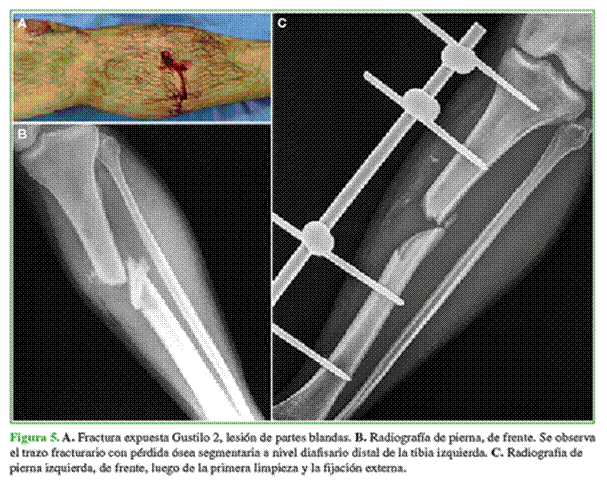

Varón de 40 años con fractura expuesta de tibia izquierda, fractura expuesta de rótula derecha y fractura medio-diafisaria de radio derecho, con pérdida ósea en la tibia, como consecuencia de un accidente de tránsito. El tratamiento inicial consistió en limpieza y resección del tercer fragmento desvitalizado y contaminado más colocación de fijador externo (Figura 5). El paciente quedó internado por un hematoma esplénico en la Unidad de Terapia Intensiva. A las 48 h, se lo evaluó nuevamente y se aisló Streptococcus viridans por lo que se le indicó ampicilina durante 45 días.

Dos semanas después se procedió a la osteosíntesis del antebrazo derecho más enclavado con antibiótico en la tibia izquierda. Al concluir el tratamiento antibiótico, se efectuó una biopsia por punción, todas las muestras fueron negativas y se procedió a la reconstrucción esquelética (Figura 6).